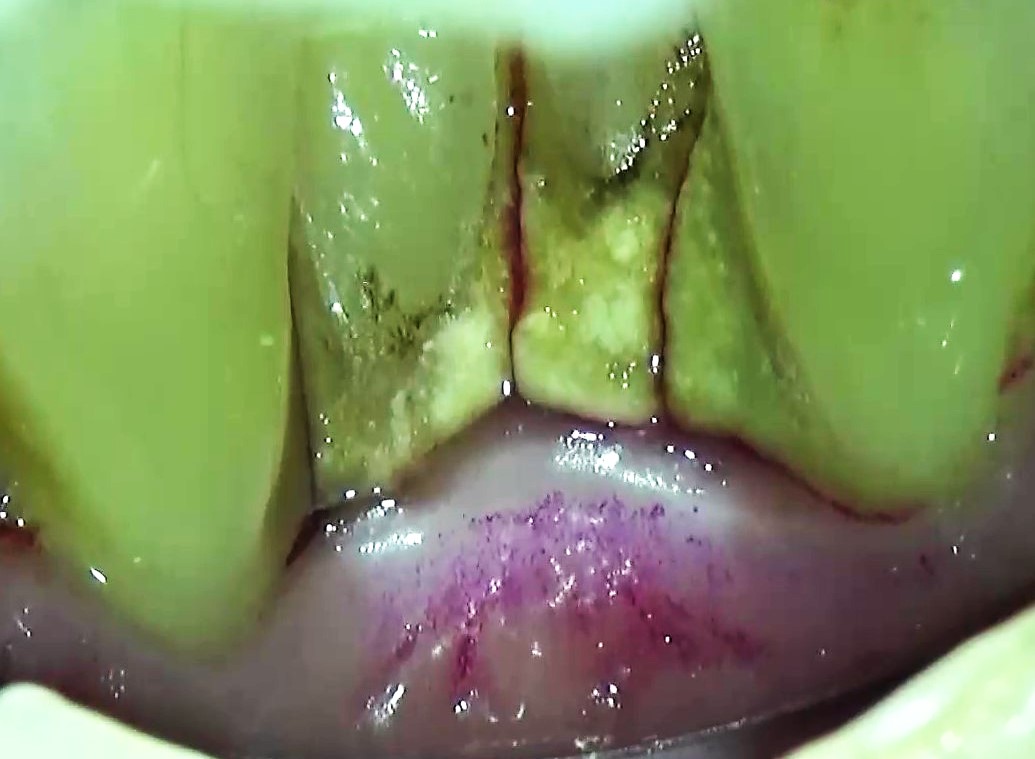

【歯周専門治療】歯周ポケット内の歯石除去

こんにちは! 南館歯科クリニックの歯科衛生士 山崎です。 歯周病治療中の実際の映像です。 https://youtu.be/1uqB9yPVELY 歯周ポケット内に入り込んだ歯石の除去を行っています。…

【歯周専門治療】歯石除去

こんにちは! 南館歯科クリニックの歯科衛生士 山崎です。 歯周病や虫歯が悪化する原因の一つは、歯医者に行く機会を逃すことです。 そしてそれは、セルフケアが正しく行えないことに繋がります。 https:…